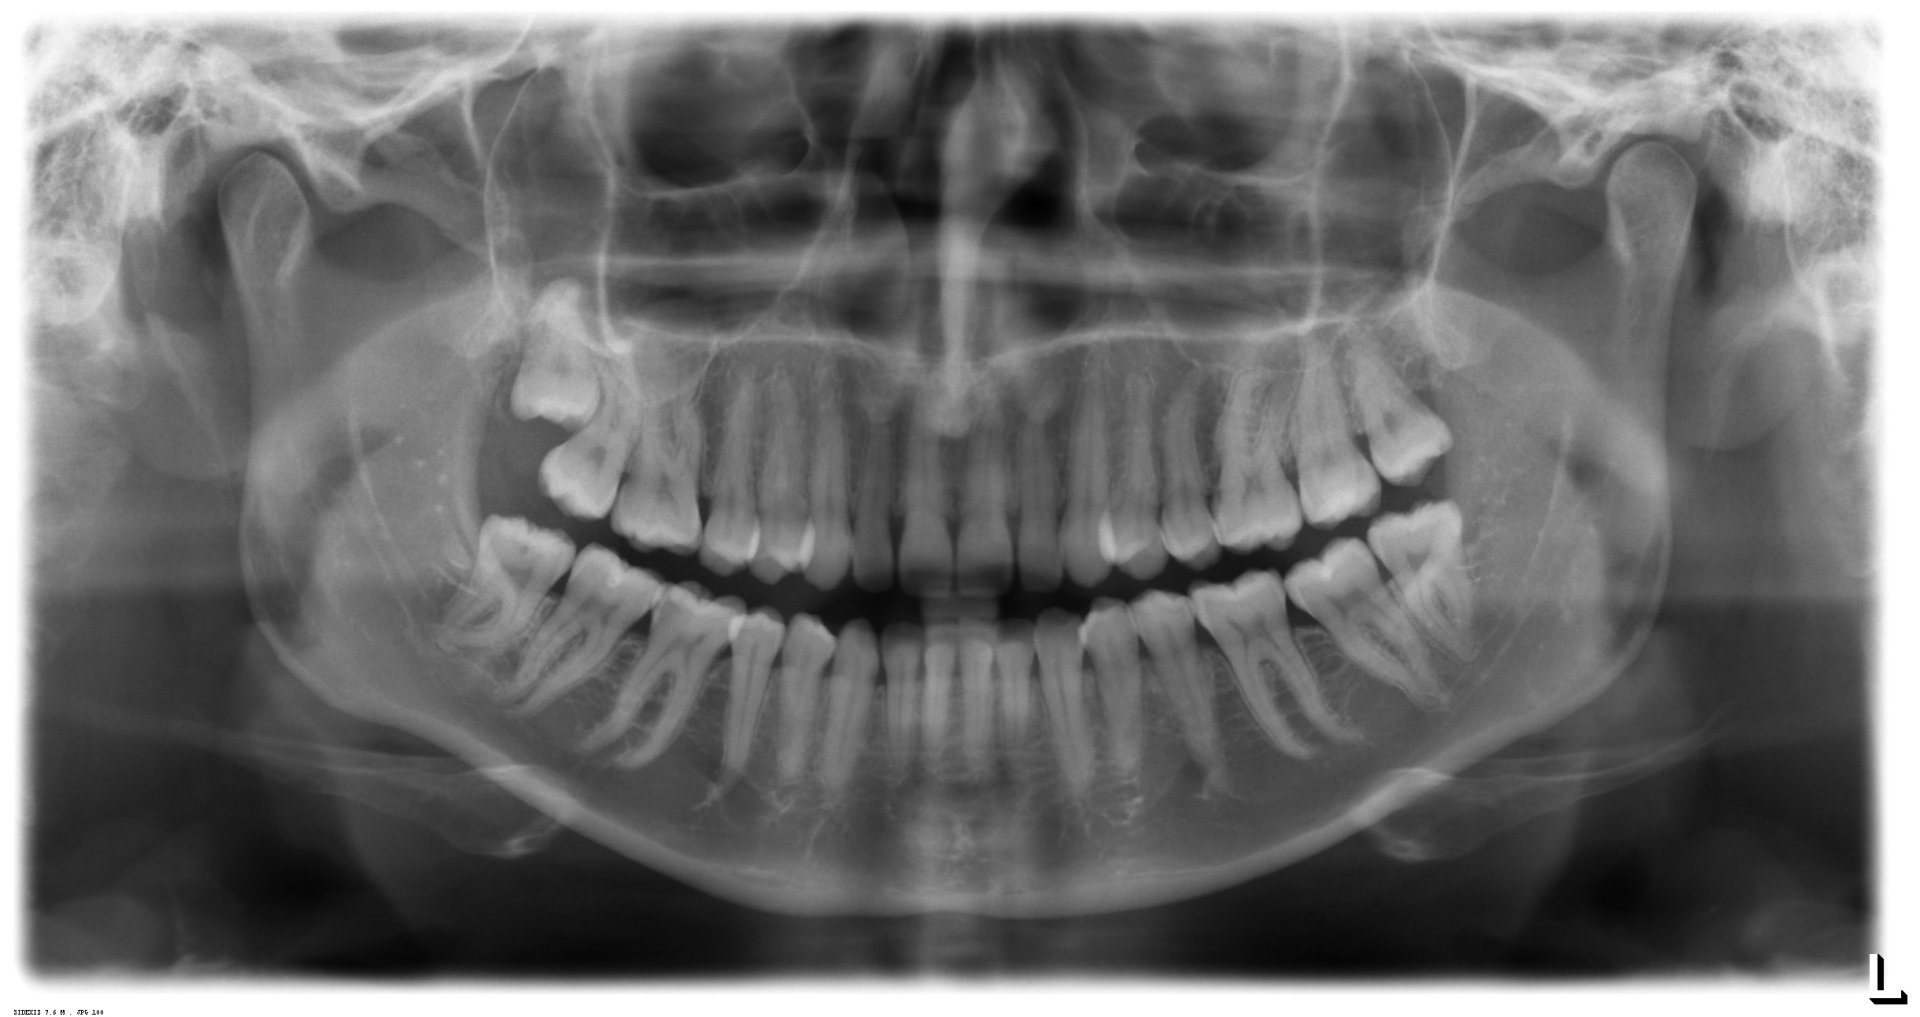

¿Cuándo se deben extraer las muelas del juicio?

Quistes odontogénicos, tumores

Caries (también en el diente de enfrente)

Antes de la disgnatia

La osteotomía conduce a través de la región de la muela del juicio.